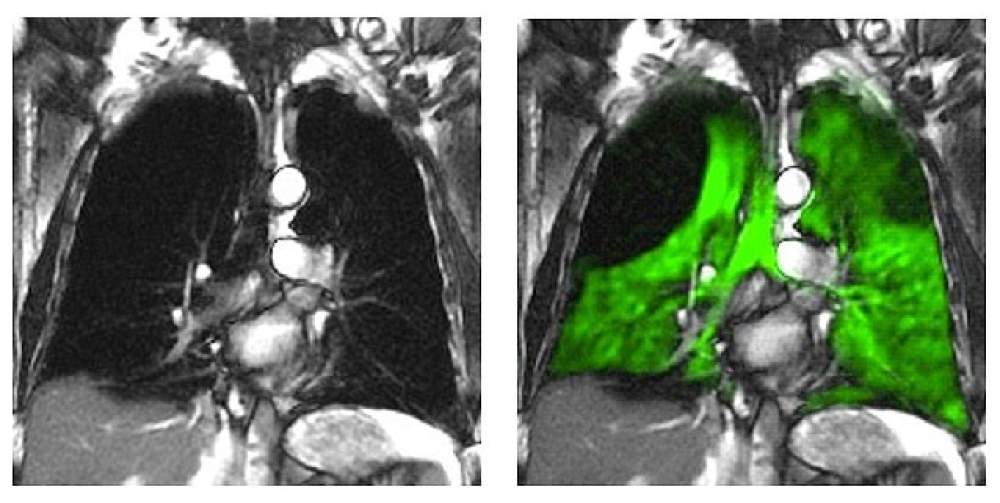

Urenco Stable Isotopes has signed a new contract to supply enriched Xenon-129 for medical purposes. Pending Food and Drug Administration approval, the enriched Xenon can be used to enhance considerably lung MRIs, allowing for the detection of abnormalities and diseases at a far earlier stage.

The enriched Xe-129 isotope (more than 80% enriched) becomes part of a gas mix. The gas mix is inhaled by the patient and while inside the lungs, an MRI is performed. Before the patient inhales the gas mix, the Xenon is 'hyperpolarized' (negative charge of the cell membranes increased). This improves the MRI scan by a factor of 100,000, making the lung structures highly visible. As a result, various abnormalities and diseases become detectable at a much earlier stage than with the current method.